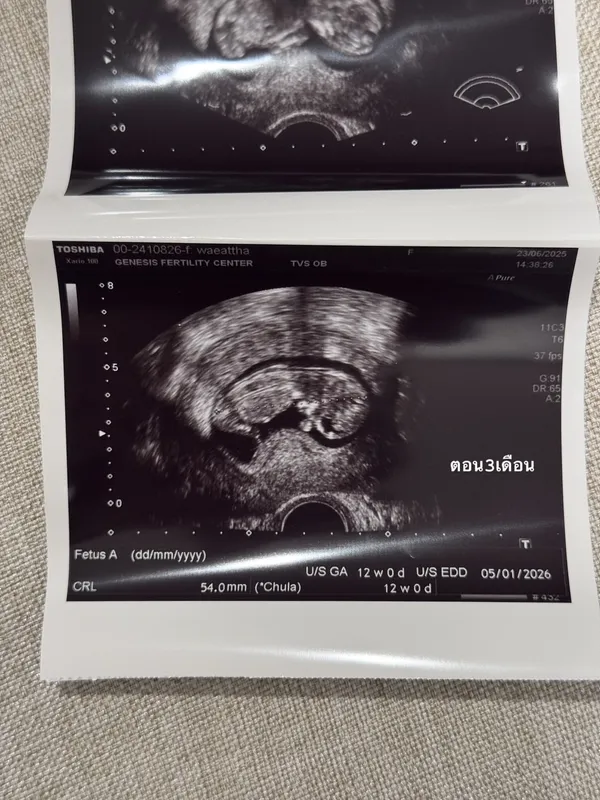

"ช่วงนี้หายๆไปเพราะว่าเนยมีน้องแล้ว 👼🏻 ในรูปคือประมาณ3เดือนตอนนี้ก็เกือบจะ4เดือนแล้ว ท้องป่องแล้ว😅 ต้องบอกว่าจะมีลูกคนนึงไม่ง่ายเลยเข้าใจว่าตัวเองแข็งแรงสุขภาพดีมาก ดูแลตัวเองมาอย่างดีมากๆ อาหารการกินคือคลีน ไม่ดื่ม ออกกำลังกายสม่ำเสมอ นอนไม่ดึก แต่ปรากฏว่า เนยบ้ายบายน้องไปถึง 2 รอบ จนแปลกใจมากจริงๆเลยตัดสินใจไปหาคุณหมอมิงค์ ที่ @gfc.bangkok พอตรวจปรากฏว่า เนยละก็สามี มีโรคทางพันธุกรรมแฝงทั้งคู่ (เลยรู้สึกว่าก็โชคดีที่น้องบ้ายบายไปถึง2รอบเพราะถ้ารอดมาชีวิตก็คงลำบาก) โอกาสที่เด็กจะออกมาสมบูรณ์มีแค่25%เท่านั้น ซึ่ง%ที่เหลือคือเป็นโรคกับเป็นโรคแฝงแบบเนยที่ใช้ชีวิตปกติจนโตได้แต่เราก็จะมียีนที่ผิดปกติติดตัวส่งทอดไปสู่รุ่นอื่นๆได้ ซึ่งเนยเลือกที่จะให้ลูกสมบูรณ์100%เลยดีกว่า เลยเริ่มทำ ICIS กับทางคลีนิค ทั้งคัดโครโมโซม ตรวจคัดโรค และหลังใส่ตัวอ่อนก็ทำ NIFTY อีก (คือต้องเพอร์เฟคละมั้ย555) ต้องบอกว่าคุณหมอมิ้งค์ดูแลดีมากๆ ตั้งแต่วันแรกไปจนวันสุดท้ายของกระบวนการเลย รวมไปถึงพยาบาลทุกคนให้คำปรึกษาละรับฟังอารมณ์ของเราเป็นอย่างดี😅 ส่วนขั้นตอนนั้นก็ใช้ความอดทน..55 ไม่เจ็บหรอกแต่จุกจิกเหลือเกินต้องกินยาสอดยาฉีดยาตัวเองให้ตรงเวลาเสมอไปทำงานทำอะไรต้องรีบกลับให้ทันเวลาฉีดยา

สำหรับเนยเป็นการทำ ICIS ครั้งแรกแล้วก็ประสบความสำเร็จเลย ไม่ต้องทำหลายๆรอบให้ท้อใจ ตอนนี้น้องสมบูรณ์แข็งแรงมากแค่3เดือนก็ดิ้นเก่งซะแล้ว👼🏻 ต้องขอบคุณ GFC มากๆที่ทำให้ทุกอย่างราบรื่นจริงๆ